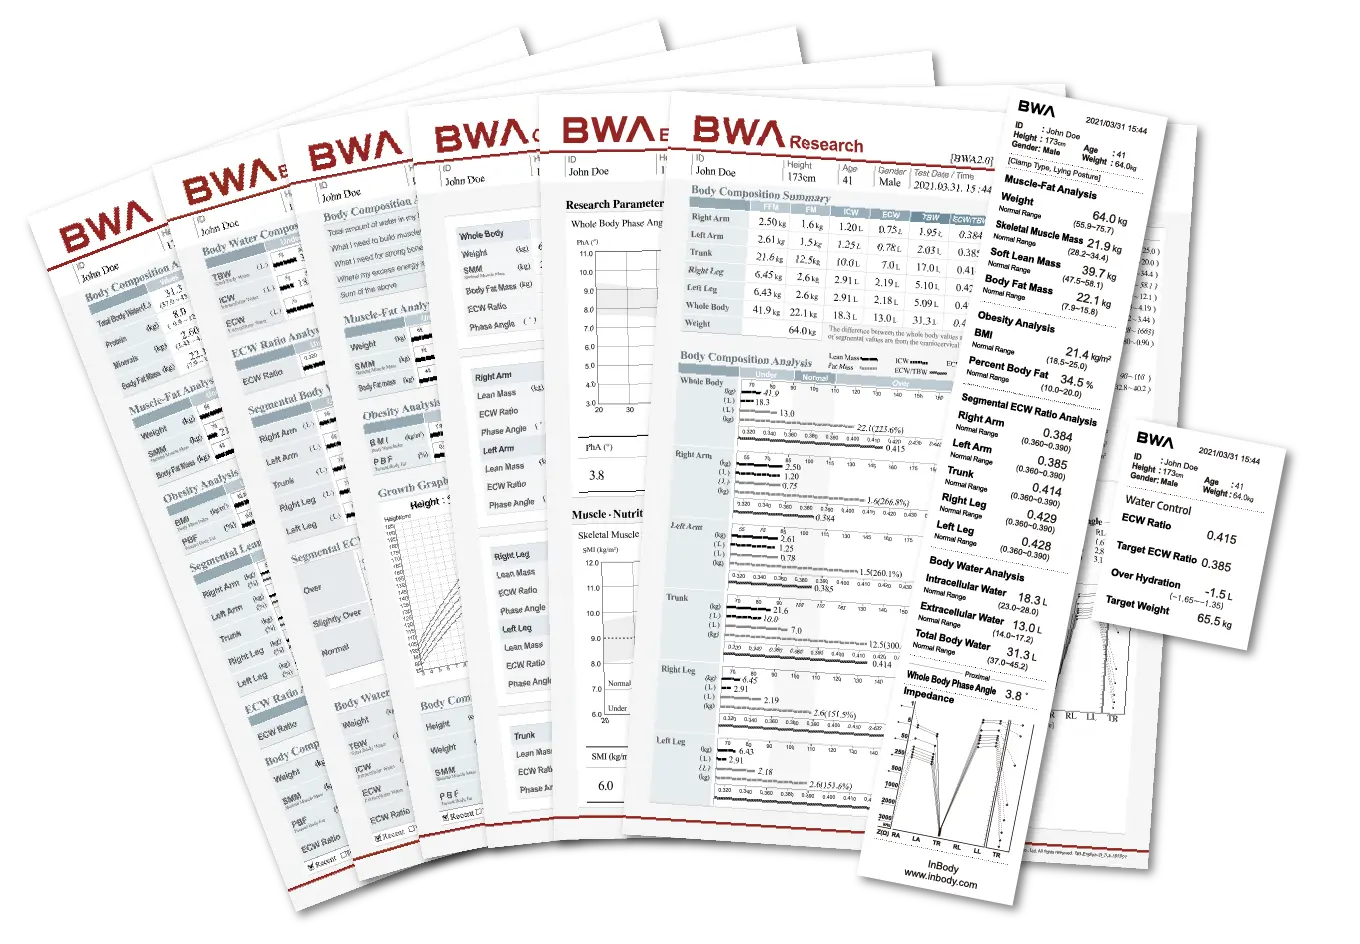

7 برگه نتایج مختلف برای تجزیه و تحلیل عمیق

7 برگه نتایج مختلف را برای برآوردن تمام نیازهای محققان ما ارائه می دهد. ارزیابی، تحقیق، مقایسه، چربی احشایی، ترکیب بدن (برای کودکان) و برگه نتایج آب بدن موجود است.